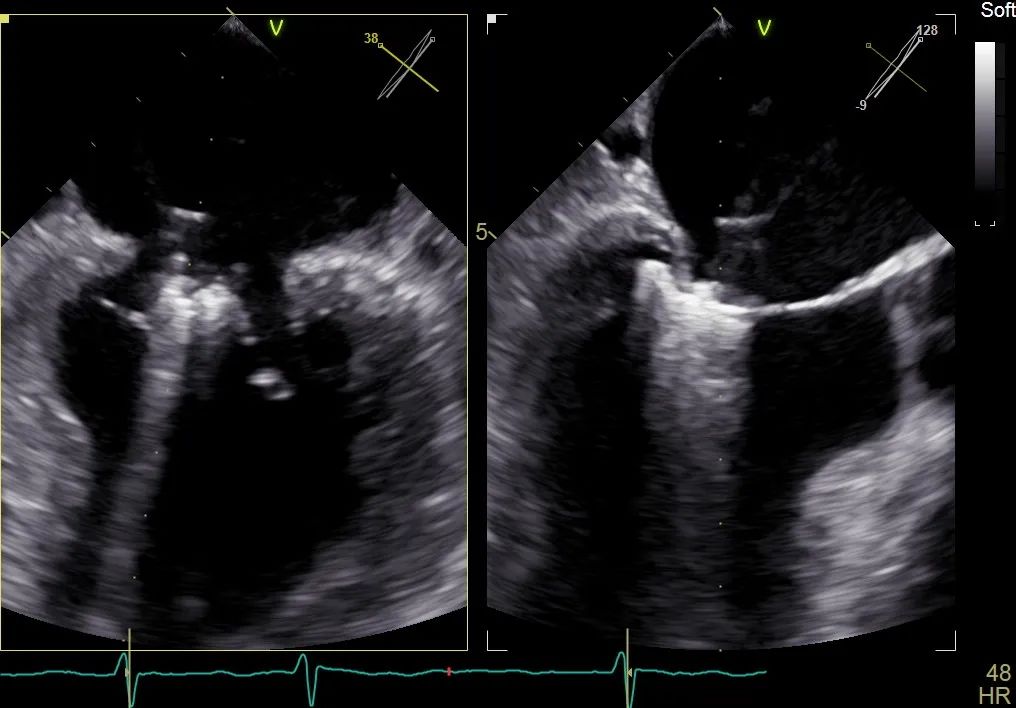

二尖瓣在收缩期变成双孔状,反流有效减小

周浩主任继续在食道超声影像引导下进行高难度操作,在第一个二尖瓣夹内侧再置入第二枚二尖瓣夹。

再次反复测试第二枚二尖瓣钳夹的稳定性,超声复查提示二尖瓣反流明显改善,平均跨瓣压差4 mmHg